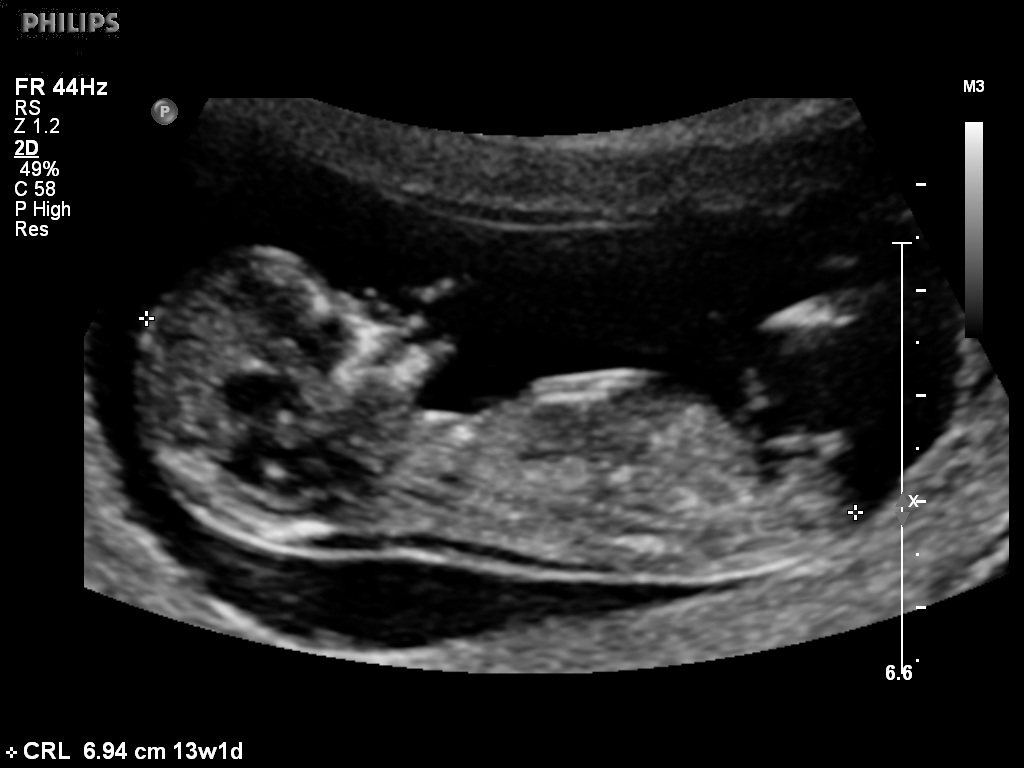

Male gender may already be reliably determined when crl ≥ 55 mm (gestational age ≥ 12+0).

Whats the accuracy of sonographic determination of fetal gender study. Full text ultrasound measurement learning of fetal sex. Biomedical papers of the medical faculty of the university palacky, olomouc, czech republic (2012) 5. Early baby gender predictor explained 2019. Updated on october 18, 2008. It's the grainy, black and white image that makes it all seem so real and we've found four. Gender confirmed by harmony test! 12 weeks 5 days ultrasound/ gender reveal.

My baby boy in 12 week scan | gender prediction week 12 ultrasound. Ramzi and nub theories, nub and skull. Nub method has very high accuracy when measuring angle of nub compared to spine! Ultrasound imaging performed in the 11th and 12th weeks of pregnancy for fetal gender identification identified the fetus either as a girl, a boy, or as a the sagittal sign for sonographic prediction of fetal gender in the early second trimester is described and its sensitivity and accuracy evaluated. You must also remember that a nub analysis before 12 weeks of pregnancy, especially for babygram can give you a reliable prediction of your baby's gender. Ultrasound and gender detection gender is determined by visually inspecting the ultrasound several studies have been conducted to determine the accuracy of gender prediction at different at 12 weeks, 99% of male gender predictions were correct, and 91% of female predictions were. But if baby is only measuring 12 weeks exactly it's still early and there is still time to change. Check out my designer online children's. Experts at babygram use the nub theory to thoroughly analyze your ultrasound. 12 week ultrasound for gender reveal. 12 week ultrasound gender prediction mp3 & mp4. Biomedical papers of the medical faculty of the university palacky, olomouc, czech republic (2012) 5. My mom bawled her eyes out and you can hear.